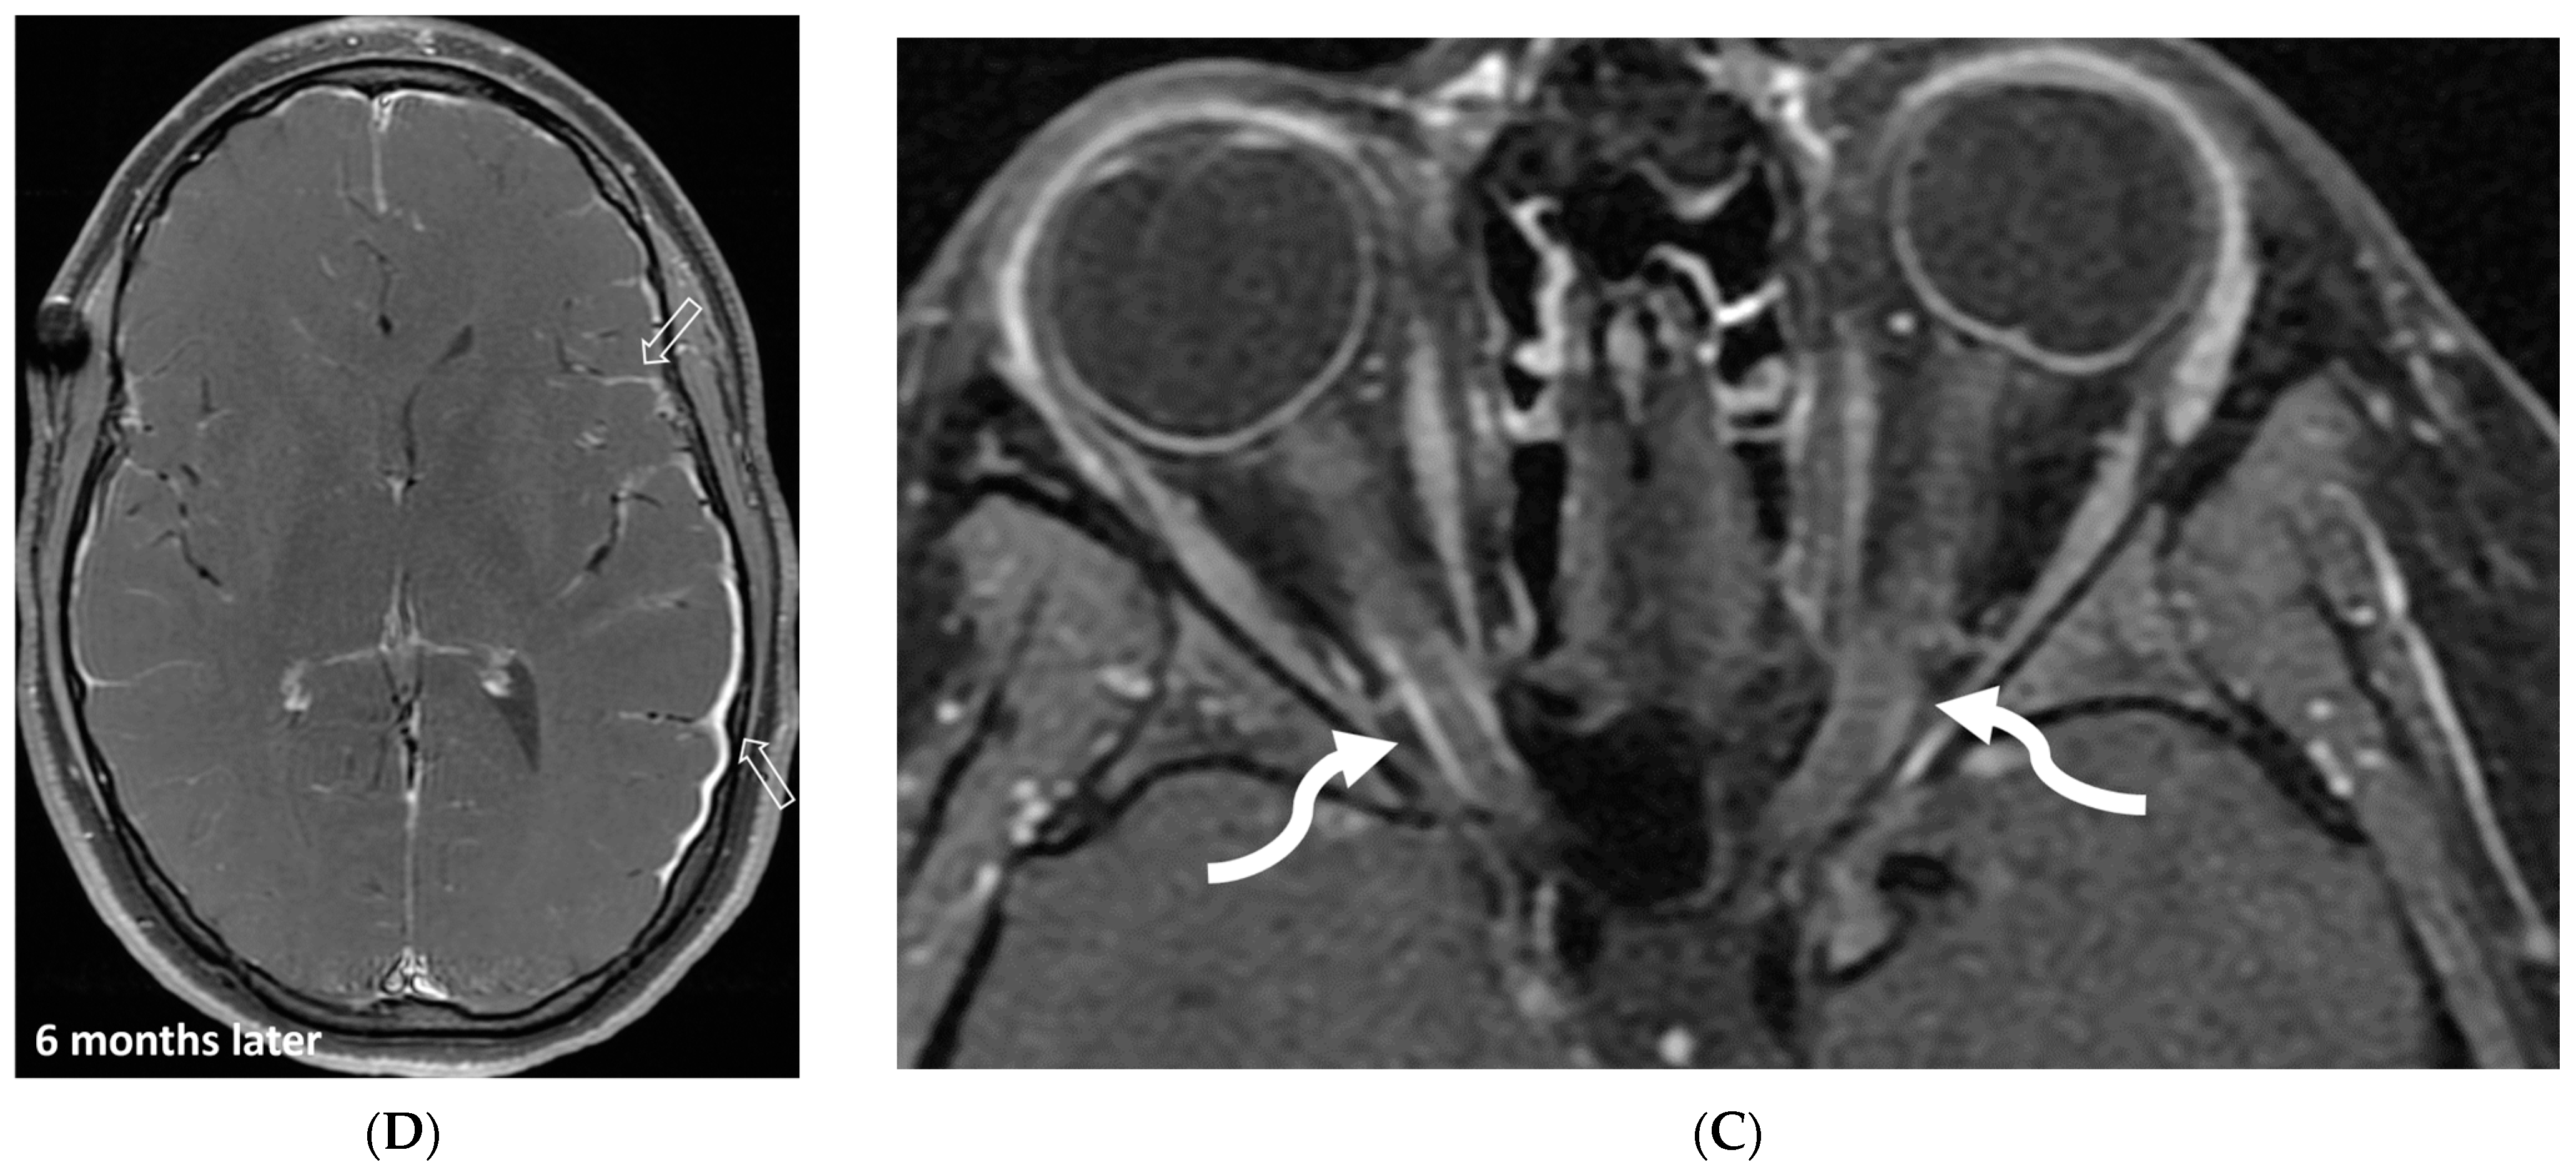

Figure 6.

Axial FLAIR (A), Axial T2 orbits (B), Axial T1 orbits post contrast (C) and axial T1 post contrast (D): 13-year-old female with headache and blurred vision. Abnormal FLAIR hyperintensity involving the left parieto-occipital periventricular white matter (arrow), and bilateral cerebellar hemispheres. Bilateral papilledema (black arrow) and edematous left optic nerve (dashed arrow). Peripheral optic nerves/optic sheath enhancement in the posterior aspect (curved arrows). Demyelination, infectious and metastatic processes were considered. MRI brain 6 months later with persistent symptoms demonstrates patchy and asymmetric pachymeningeal and leptomeningeal enhancement (open arrows). Pathology: Diffuse Leptomeningeal Glioneuronal Tumor.